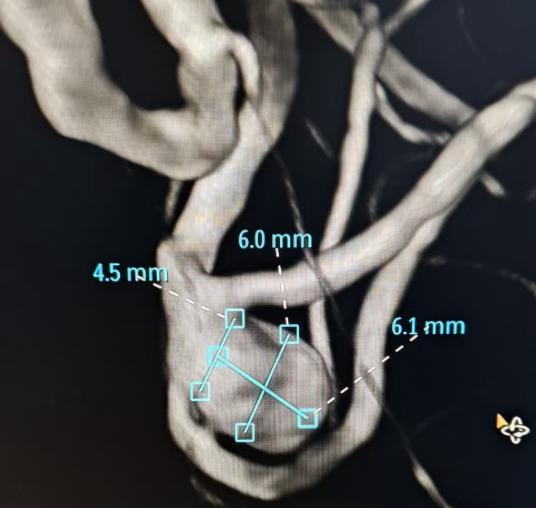

近日,面对一位古稀老人颅内破裂的“不定时炸弹”——复杂脑动脉瘤,我院神经外科团队成功应用全球前沿的自膨式动脉瘤瘤内栓塞器(WEB) ,完成了我院首例该技术下的动脉瘤精准介入治疗。 紧急救治 古稀老人突发“颅内炸弹” 71岁的张先生(化名)突发剧烈头痛伴右侧肢体乏力,经120紧急送入我院。急诊迅速启动卒中绿色通道,经头部CT及CTA检查,诊断为“广泛蛛网膜下腔出血、左侧大脑中动脉分叉部动脉瘤”。此类动脉瘤破裂风险极高,如同颅内的“不定时炸弹”,治疗刻不容缓。 术前颅脑CT见广泛蛛网膜下腔出血 CTA见左侧大脑中动脉分叉部宽颈动脉瘤 创新破局 全球新技解难题 神经外科介入团队立即组织多学科讨论,详细研判病情,制定了开颅夹闭与微创介入栓塞两套方案,家属明确选择微创手术方案。面对位于复杂分叉处且瘤颈宽大的动脉瘤,团队决定应用全球前沿的自膨式动脉瘤瘤内栓塞系统(WEB)进行治疗。在神经外科、介入中心与麻醉科的通力协作下,成功将自膨式动脉瘤瘤内栓塞系统(WEB)装置植入动脉瘤腔内,完成栓塞治疗,历经2小时。术后,造影显示动脉瘤完全隔绝,载瘤动脉通畅良好,危机解除。 技术优势 瘤内扰流新选择 自膨式动脉瘤瘤内栓塞系统(WEB)装置形似精密编织的迷你网篮,专为分叉部宽颈动脉瘤设计。相较于传统支架辅助栓塞,自膨式动脉瘤瘤内栓塞系统(WEB)技术体现了神经介入领域的重要创新: 操作简化: 单一器械即可完成治疗,流程更简洁。 安全性提升: 避免支架植入,降低了血栓等并发症风险。 患者受益: 术后无需长期服用抗血小板药物,减轻了身心及经济负担。 此例自膨式动脉瘤瘤内栓塞系统(WEB)植入术的成功开展,标志着我院在复杂脑动脉瘤微创治疗领域取得新突破,为患者提供了高效的治疗选择。作为国家卫健委能力建设和继续教育神经外科建设中心,贵州航天医院神经外科将持续依托优质资源,深化对外协作,以技术创新护航百姓健康。 神经外科专家简介 廖洪民 神经外科党支部书记、主任,主任医师 临床擅长:从事神经外科临床工作30年,对颅脑损伤、脑肿瘤、脑血管病等具有丰富诊疗经验,擅长救治重症颅脑创伤、脑出血微创治疗、脑肿瘤显微手术治疗、脑立体定向手术等。 中国医师协会神经外科分会专科认证医师、贵州省医学会神经外科分会青年委员、遵义市医学会神经外科分会常务委员、遵义市中西医结合学会脑心同治专业委员会常务委员、中国生命关怀协会脑卒中救治及康复照护专业委员会委员、贵州省脑损伤评价质控中心专家库成员、遵义市脑损伤评价医疗质量控制中心专家。 朱家伟 神经外科副主任医师 临床擅长:从事神经外科工作26年,擅长颅脑损伤救治及脑出血微创手术。 遵义市医学会神经外科分会委员、遵义市中西医结合学会脑心同治专业委员会常务委员。 黄建军 神经外科副主任医师 临床擅长:从事神经外科工作20年,对神经外科常见病、急危重症有丰富诊疗经验,熟练掌握神经外科微创手术。 神经外科科室简介 基本情况 贵州航天医院神经外科于2008年独立建科,是首批国家卫健委能力建设和继续教育神经外科建设中心,贵州省神经外科介入联盟单位。现有专业技术人员17人,其中高级职称4人,中级5人,初级7人。 科室配备STORZ神经内镜系统、德国莱卡手术显微镜,国产西山开颅动力系统、蛇牌双极电凝、Mayfield头架等颅脑手术设备,以及无创和有创颅内压监护仪、正中神经刺激仪、脑循环康复治疗仪、排痰机、下肢康复训练器、气垫床、多参数监护仪等现代化医疗设备,为病区各种急、危、重患者的观察、监护和治疗保驾护航。 专科特色 (一)脑出血微创手术治疗 应用范围:各种病因导致的自发性脑出血(高血压脑出血、脑淀粉样血管病相关脑出血、抗凝药物相关脑出血等)。 技术优势:微创、精准、恢复快。 (二)颅脑病变显微切除术 应用范围:颅内各种占位性病变(脑囊肿、脑肿瘤等)。 技术优势:精确度高、创伤小、恢复快。 (三)颅脑创伤综合救治 应用范围:各种类型的颅脑损伤、创伤性颅内血肿及颅脑创伤并发症、后遗症等。 技术优势:快速精准诊断、个体化手术与监护、早期康复干预,伤者病死率低、并发症少。